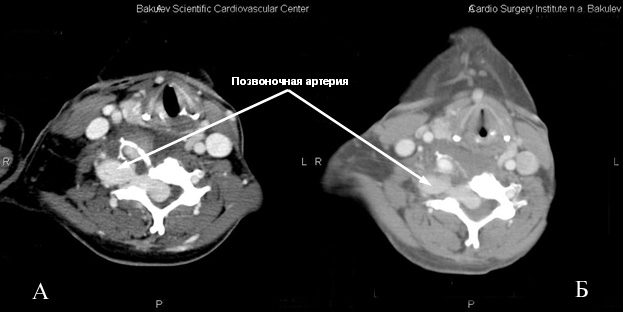

Спиральная компьютерная томография брахиоцефальных артерий с внутривенным болюсным введением Омнипака 300- 80,0: Грудная аорта без видимой патологии, обычного диаметра, левые общая сонная и подключичная артерии расположены типично. Брахиоцефальный ствол смещен кпереди и вправо. Правая общая сонная артерия диаметром 7 мм, правая подключичная артерия в устье имеет диаметр10 мм. От нее отходит правая позвоночная артерия диаметром 10 мм (рис 1).

Правая позвоночная артерия после отхождения от подключичной артерии отклонена несколько вправо, идет назад, делая S-образный изгиб загрудинно резко неравномерно расширяется до 25 мм, далее расширенная артерия «делает» петлю, образуя мешковидное сосудистое образование распространяется вниз в грудную клетку до правой ветви легочной артерии, вверх до С5, размерами 87×40 мм. После образования петли позвоночная артерия по передней поверхности тела позвонка сужается до 10 мм, идет косо вниз и вправо, затем снова расширяется до 27 мм и на уровне С6 входит в позвоночный спинномозговой канал (рис.1,4). Дистальнее правая позвоночная артерия расширена и извита, в позвоночном канале соединяется с резко расширенными корешковыми ветвями и также резко расширенной правой спинальной артерией (спинной мозг оттеснен влево и кзади) (рис.3). Отмечается выраженная деформация поперечного отростка С6 справа, обусловленная длительной компрессией расширенными сосудами.

Рис.1 Аксиальный срез.

А- до процедуры. Резко расширена позвоночная артерия, видны широкие анастомозы с сосудами спинномозгового канала. Резко выражена деформация поперечного отростка С6-позвонка.

Б- после процедуры.